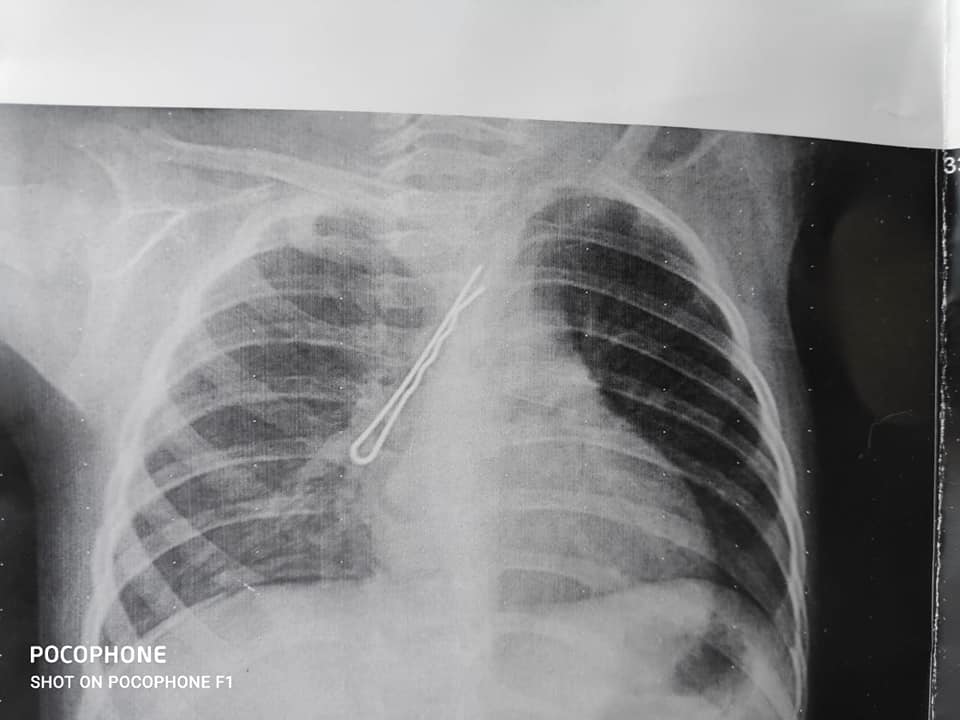

تمكن فريق طبى بقسم جراحه القلب والصدر بالمستشفى الجامعي بسوهاج، من استخراج “بنسه شعر” يبلغ طولها ٣ سم من الممرات التنفسية لطفلة تبلغ من العمر عاما ونصف.

واوضح الدكتور ايمن عبد الغفار رئيس قسم جراحة القلب والصدر ان الطفله “أ.أ.أ”حضرت من مركز البلينا إلى المستشفى فى حاله حرجة جداً بعد دخول “بنسة شعر”بممرات الجهاز التنفسى، حيث تم اجراء الفحوصات والتحاليل والأشعة اللازمة لتحديد موضع البنسه، حيث تمكن الفريق من الدخول بمنظار الشعب الدقيق واستخراج الجسم الغريب من الممرات الهوائية، مشيرا الي ان القسم يمتلك مجموعة من مناظير الشعب الهوائية تخدم المواطنين وساهمت في إنقاذ الآلاف من ابناء المحافظة والمحافظات المجاورة.